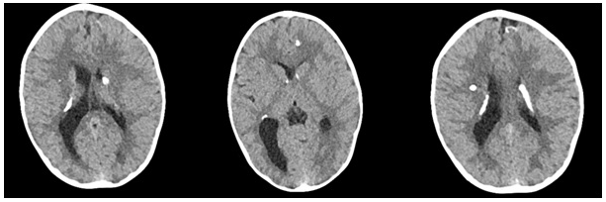

Congenital Toxoplasmosis and Cytomegalovirus Coinfection in a 13-Months Old Asymptomatic Girl

Özge Kaba, Manolya Kara, Selda Hançerli Törün, Cihan Yeşiloğlu, Tarkan Ikizoğlu, Özgül Altintaş, Baki Mudun7 and Ayper Somer. 13(10): 01-04.